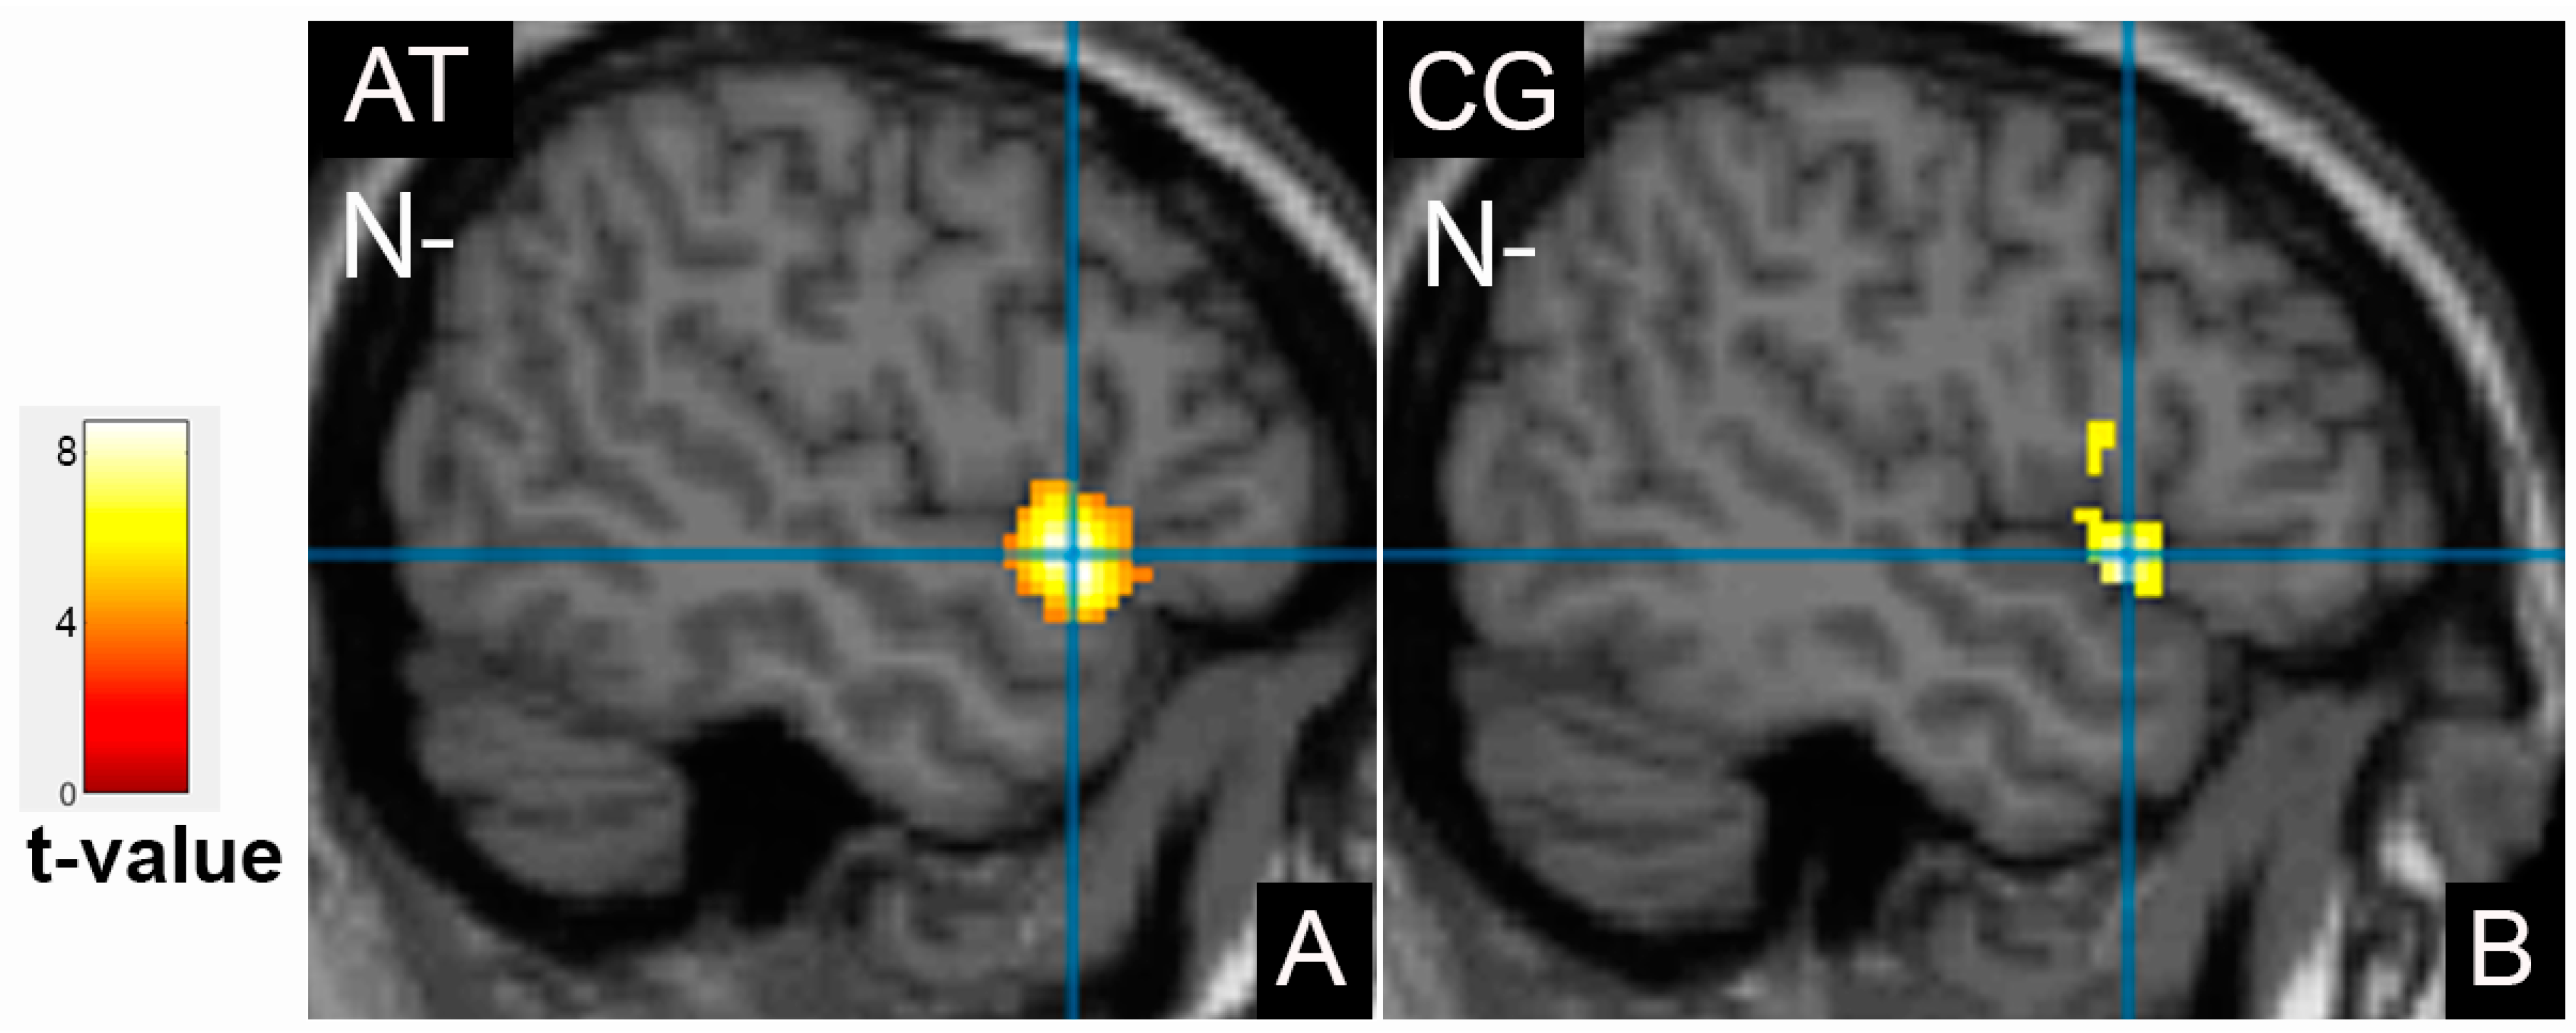

3.2. Comparison of Brain Activation Patterns in Patients before and after Treatment

3.3. Comparison of Brain Activation Patterns in Patients before Treatment and Healthy Controls

| Cluster Location | Emotion | Extent | t-Value | p (FWE Corrected) | MNI Coordinates |

|---|---|---|---|---|---|

| Patients group after therapy | |||||

| Frontal cortex | |||||

| Right inferior frontal gyrus | N | 1390 | 10.97 | <0.001 | 38;4;28 |

| Right middle frontal gyrus | N- | 386 | 5.51 | 0.008 | 46;30;26 |

| Occipital cortex | |||||

| Left fusiform gyrus, BA37 | N | 1532 | 6.48 | <0.001 | −40;−68;−20 |

| Right fusiform gyrus, BA37 | N | 1861 | 7.44 | <0.001 | 44;−58;−24 |

| Temporal cortex | |||||

| Left superior temporal gyrus, BA22 | N- | 420 | 5.94 | 0.005 | −48;12;−4 |

| Control group, cortical activation | |||||

| Right middle frontal gyrus | N | 2228 | 8.91 | <0.001 | 54;14;34 |

| Right inferior frontal gyrus, precentral gyrus | N- | 946 | 6.05 | <0.001 | 42;6;30 |

| Right inferior frontal gyrus | P+ | 280 | 7.29 | 0.041 | 46;36;8 |

| Left inferior frontal gyrus, insula | P+ | 358 | 5.93 | 0.014 | −36;24;4 |

| Limbic lobe | |||||

| Left amygdala | N | 298 | 8.29 | 0.009 | −28;0;−24 |